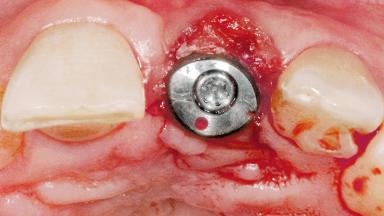

Late Flapless Placement of an Implant in a Maxillary Left Central Incisor Site

A 39-year-old male patient presented with a chief complaint of discomfort and gingival discoloration around his maxillary left central incisor. He was in good general health and was a non-smoker. His past dental history was significant because of the traumatic fracture of tooth 21 in a sporting accident at age 13. Initial dental treatment included endodontic therapy and a full-coverage restoration. The patient became symptomatic 5 years later, when structural failure of the tooth resulted in the dislodgment of the crown. Endodontic retreatment, apical surgery, and post-and-core restoration were performed.

Type of Implants One-Piece

Attachment One-Piece

Soft Tissue Grafting Simultaneous